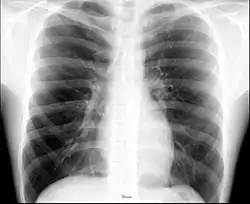

X-ray image of the chest showing the internal anatomy of the rib cage, lungs and heart as well as the inferior thoracic border–made up of the diaphragm.

An X-ray of a human chest area, with some structures labeled

The contents of the thorax include the heart and lungs (and the thymus gland); the (major and minor pectoral muscles, trapezius muscles, and neck muscle); and internal structures such as the diaphragm, the esophagus, the trachea, and a part of the sternum known as the xiphoid process). Arteries and veins are also contained – (aorta, superior vena cava, inferior vena cava and the pulmonary artery); bones (the shoulder socket containing the upper part of the humerus, the scapula, sternum, thoracic portion of the spine, collarbone, and the rib cage and floating ribs).